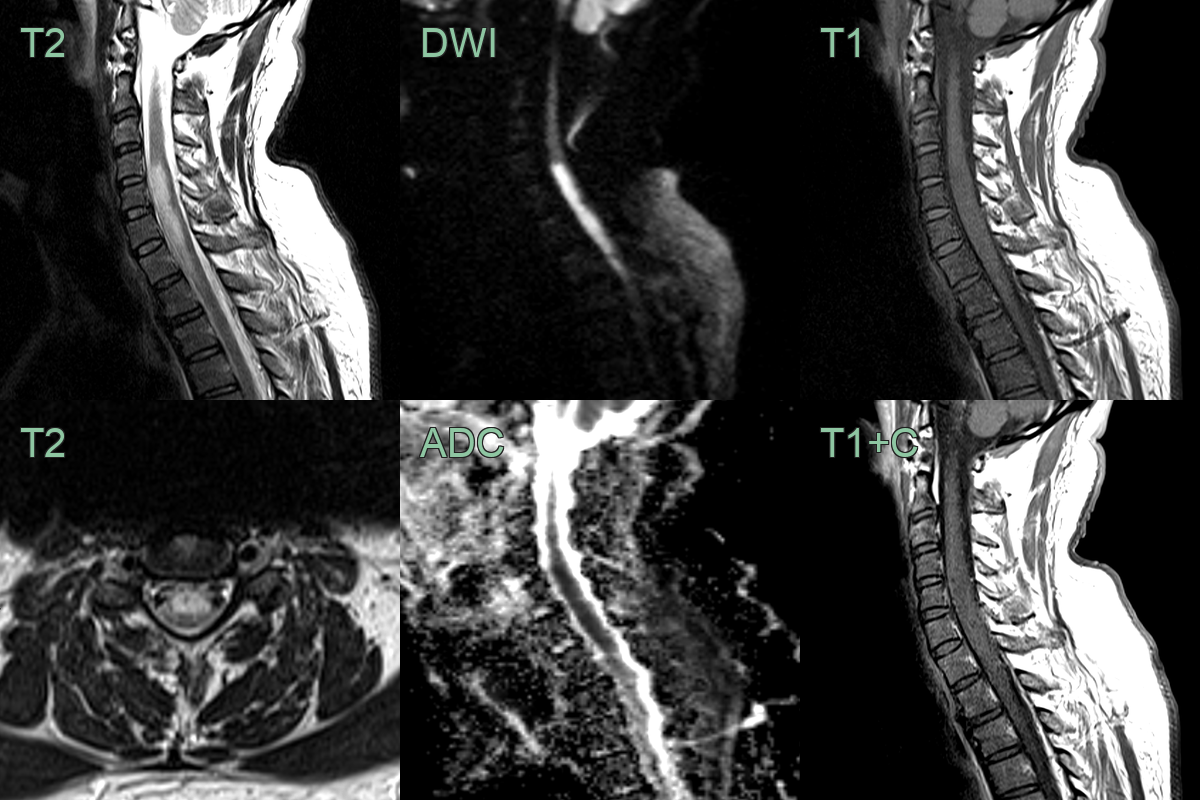

Spinal cord infarction

- A 50-year-old patient presented with acute upper back pain and quadriparesis.

- MRI showed a long segment lesion with diffusion restriction without contrast enhancement.

- The involvement of the anterior half of the cord was typical of an acute cord infarct in the territory of the anterior spinal artery.